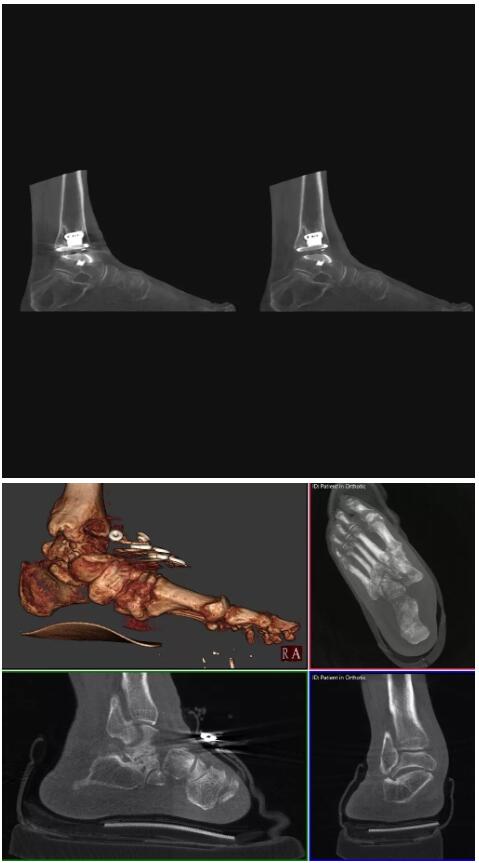

比如上面這款專用于足部和踝部掃查的CT成像系統(tǒng),患者在進行CT掃查時只需要站在上面即可,雙腳站或者單腳站都可以,當然,如果患者不是那么方便站著做完CT掃查,也可坐在上面。

這款CT掃查系統(tǒng)自帶屏蔽裝置,它的體積非常小,僅需要極小的空間即可,并不像常規(guī)CT那樣需要一間單獨的檢查室。此外,這種CT掃查的速度非??欤瑑H需30秒左右可以完成檢查,輻射劑量相對常規(guī)的CT要少許多,尤其適合醫(yī)院的骨科使用。

而患者站著做足部或者踝部做CT檢查還有個好處是,可以檢查患者在負重的情況下,骨關節(jié)的真實情況,而躺著做CT掃查時未必能看出來。負重CT掃查特別是對于受傷的運動員或者舞蹈員來說意義更大,能夠更準確地評估傷情,幫助他們盡早復原。

以下是這些“特立獨行”的CT所拍出來的圖像: